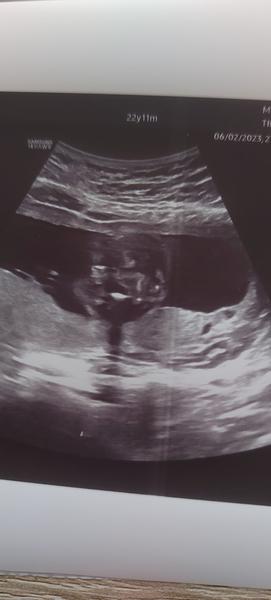

Jak zjistit pohlaví z ultrazvuku ve 21. týdnu?

Ahoj děvčata, mám na Vás takový menší dotaz. Byla jsem na ultrazvuku ve 21 tt. Pan doktor mi řekl, že pohlaví neříká, že to musím poznat sama, ale že to tam je krásně vidět. Jelikož je to mé první těhotenství, tak jsem z toho ultrazvuku zmatená a moc se v tom nevyznám. Vidítě v tom něco? 🙂 Předem děkuji.

Kavovy zrno, holka 🙂